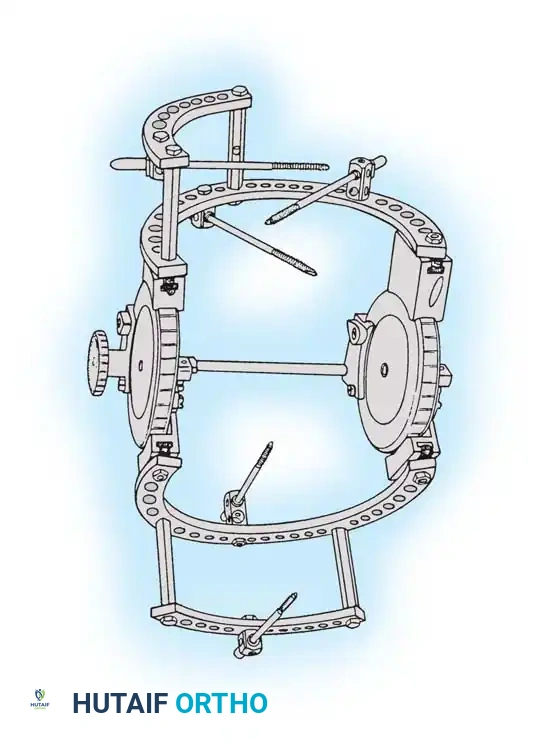

Surgical Technique: Compass Hinged Elbow External Fixator (Hotchkiss)

The ulnohumeral articulation is a highly constrained hinge joint. Because only slight movement of the instant center of rotation occurs during flexion and extension, locating the exact rotational axis is the most critical step in applying a dynamic fixator.

Assembly of the Hinge Block

The Compass hinge utilizes a precision worm gear to provide controlled displacement for stretching through extremes of motion.

Fig. 58-27 Design features of the hinged elbow external fixator, noting the built-in 7 degrees of valgus to approximate the distal humerus anatomy.

Preoperative assembly is vital. The hinge block must be configured so the large block sits medially. The differential block height accommodates the average 7 degrees of distal humeral valgus, ensuring the upper ring remains perpendicular to the humerus while the axis of rotation is perfectly aligned.

The Compass hinge arrives assembled for a right arm.

Fig. 58-28A The Compass hinge in its default right arm configuration.

To convert it for a left arm, remove the proximal 5/8-inch ring by loosening the T-bolts. Remove the proximal blocks using a 9/64-inch hex wrench.

Fig. 58-28B Switch the blocks to the opposite wheel, rotating each block 180 degrees so the tilt is reversed.

Resecure the blocks tightly and replace the proximal ring.